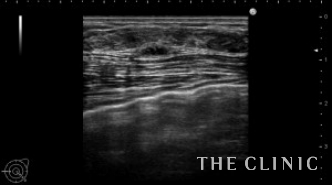

こちらは、多発するヒアルロン酸のしこり治療の症例です。

これまで2回他院でヒアルロン酸豊胸を行っていますが、たくさんのしこりができてしまい当院へ来られました。

両側の皮下、乳腺下、大胸筋内と30個以上のしこりを認めました。

一つ一つエコー下にヒアルロニダーゼを注入して吸引除去しました。

わずかに残存していますが、ほぼしこりは消失しました。

ヒアルロン酸注入によるしこりのエコー診断カルテ